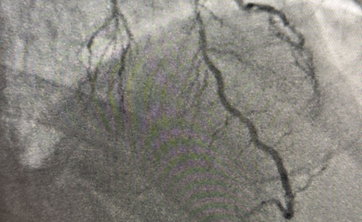

cioe0791.jpg

Zespół kardiologiczny podczas przeprowadzania złożonego zabiegu angioplastyki wieńcowej

Pod kierunkiem dr. Pawła Wnęka, we współpracy z prof. Marcinem Protasiewiczem i prof. Tomaszem Rolederem, zespół stanął przed zadaniem przeprowadzenia złożonej wieloetapowej angioplastyki wieńcowej.

mloz6989.jpg

Obrazowanie angiograficzne naczyń wieńcowych w czasie rzeczywistym

Obrazowanie NIRs – zaawansowana technologia, pozwalająca na precyzyjną wizualizację naczyń wieńcowych w czasie rzeczywistym.